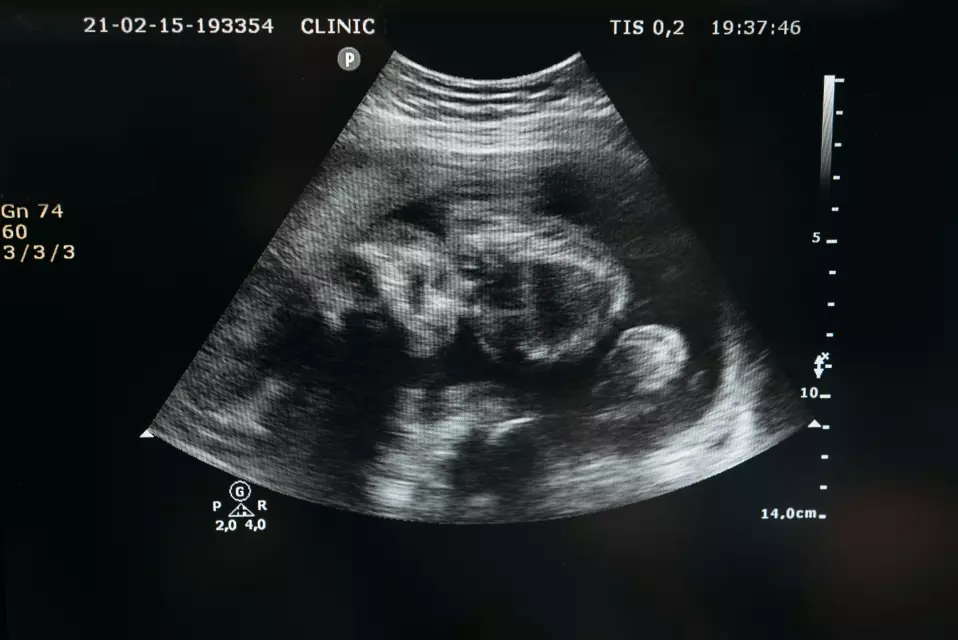

👶 Redoviti ultrazvučni pregledi

Naš tim pruža visokokvalitetne ultrazvučne preglede koji vam omogućuju da pratite razvoj vašeg djeteta u svakom tjednu trudnoće.

📌Pristup najmodernijim tehnologijama

Kroz naše usluge vođenja trudnoće u Zagrebu, imat ćete pristup najnovijim tehnologijama i medicinskim postupcima. Upotrebljavamo najmoderniju opremu za ultrazvuk i druge pretrage koje omogućuju detaljan uvid u razvoj vašeg djeteta i vaše zdravlje.